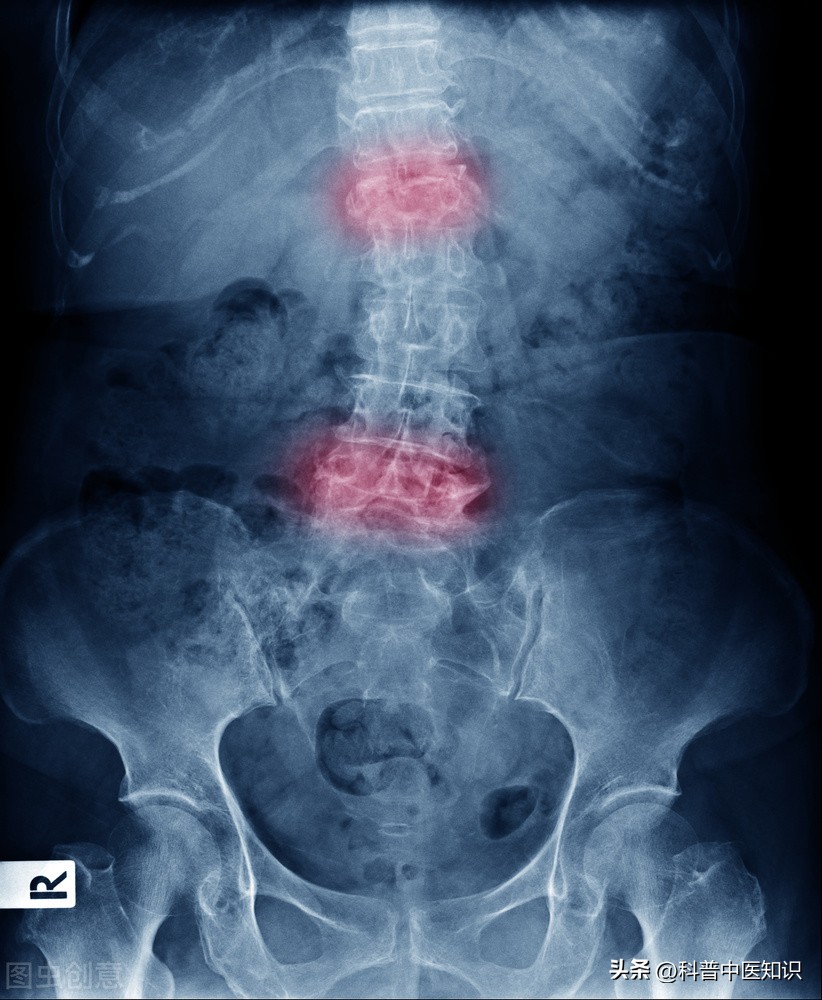

下面是著名中医焦树德教授的一则医案:一男20岁,患者半年前自觉腰髋部及双膝关节疼痛,遇热则痛减,伴僵直不舒。曾于当地医院查血沉70mm/h。予以青霉素、链霉素和炎痛喜康片等治疗无效。近日来腰髋关节痛加重,坐时尤著,腰椎僵直感明显,前弯、侧弯、后仰活动受限,双下肢无力,不能下床活动,生活不能自理。遂收入院治疗。入院后查血沉45mm/h,类风湿因子(-)。腰骶椎正侧位片示:两侧骶髂关节改变符合强直性脊柱炎。查体:腰椎旁压痛(+),腰背肌肉呈板状僵硬,双下肢肌肉萎缩,不能下地行走。舌质淡,舌苔白,脉细滑,诊断为强直性脊柱炎。

强直性脊柱炎过去被认为是类风湿关节炎的一个临床类型。后来发现,HLA-B27阳性的人群易患此病,证明了本病是一个独立的疾病。本病起病迟缓,以持续性腰或涉及胸、颈段脊柱疼痛,晨僵,活动受限,甚则出现驼背、脊柱强直、骶髂关节受损,两腿活动受限等,为主要症状的疾病。强直性脊柱炎的发病男性多于女性,且易多见于15—40岁左右的青少年及中年人。实验室检查90%以上的患者HLA—B27阳性。X线拍片显示:骶髂关节融合。对强直性脊柱炎的治疗,焦树德教授有自己独特的见解。